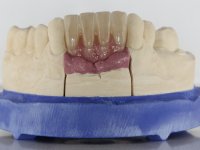

After an imaging study, the placement of two implants of 3.3 mm in diameter and 10 mm in length was planned. On the day of surgery, teeth 42 and 32 were extracted and the implant was removed. The implants were placed in the area of the alveoli, taking care to slightly lingualize their positioning. An impression was made using the open tray technique with the flap open for the fabrication of the immediate provisional bridge. While the impression was taken to the laboratory, tall healing screws were placed and the surgical wound was sutured. The patient waited 2 hours in the waiting room while the temporary bridge was made in the laboratory. An immediate screw-retained provisional bridge was placed and its seating was controlled by imaging. After 3 months, the final impression was made using an open tray technique. In this consultation, we took the opportunity to polish the temporary bridge with rubber cups so that the soft tissues could mature in better conditions. Information was collected to better characterize the monolithic structure in Zr. Color guides were used for the coronal and gingival ceramics. In the laboratory, a bridge was made in Zr. bolt-on that has been carefully characterized. After approval by the patient, it was definitively placed in the mouth. Tightening was performed with a dynamic wrench with a torque of 35 N. The holes were covered with Teflon and filled with composite resin.